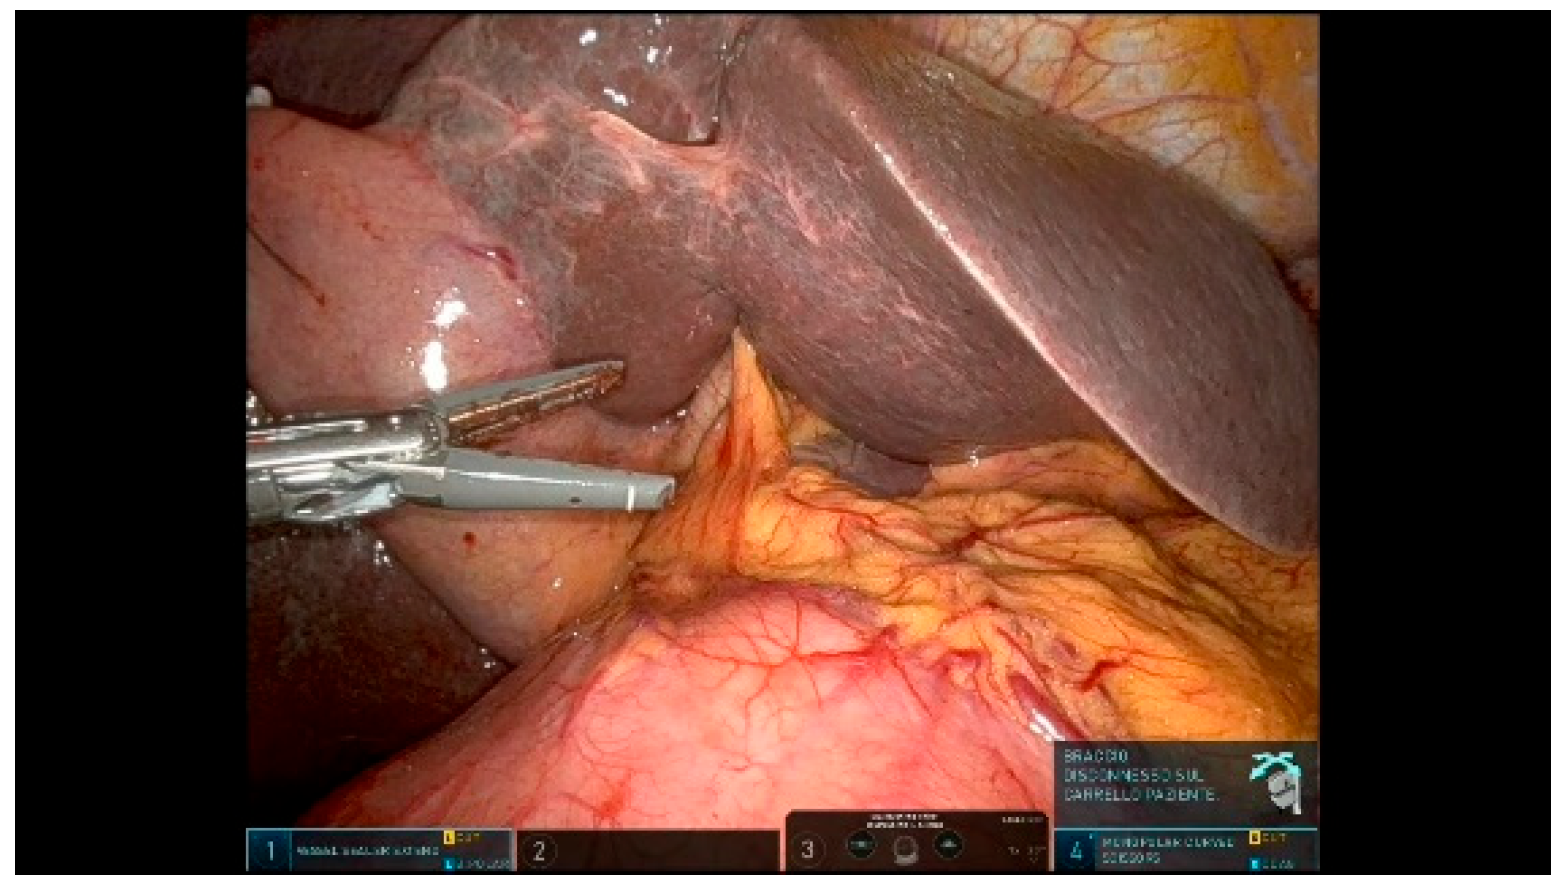

3.1.10. Step 10: Specimen Mobilization